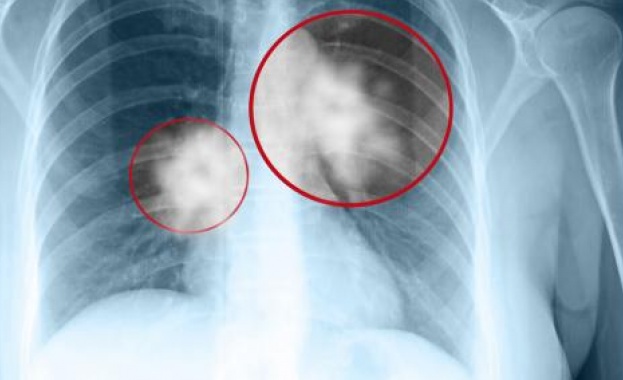

Световният ден за борбата с рака на белия дроб който се отбелязва

Световният ден за борбата с рака на белия дроб който